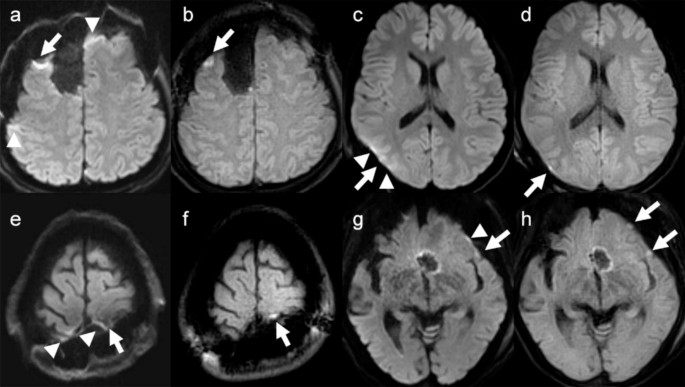

Four of the 10 acute infarct lesions or postoperative contusions were observed in patients immediately after surgery, and were difficult to find on SS-EPI DWI because of susceptibility artifacts due to air or hemorrhage (Fig. 2). No lesion was detectable on SS-EPI DWI but not on TGSE-BLADE DWI. Lesions visualized only on TGSE-BLADE DWI were verified by pixel-to-pixel comparison in FLAIR images obtained at the same time or in FLAIR images obtained at follow-up MRI.

Representative images obtained in patients who underwent surgery for brain tumor show postoperative changes related to acute cerebral infarction or postoperative contusion on postoperative day 1. It is difficult to determine whether the postoperative changes are due to acute cerebral infarction or to postoperative contusion (white arrows) and susceptibility artifact (arrowheads) in SS-EPI DWI (a, c, e, and g). Postoperative changes are clearly differentiated as acute cerebral infarction or postoperative contusion on TGSE-BLADE DWI (b, d, f, and h).